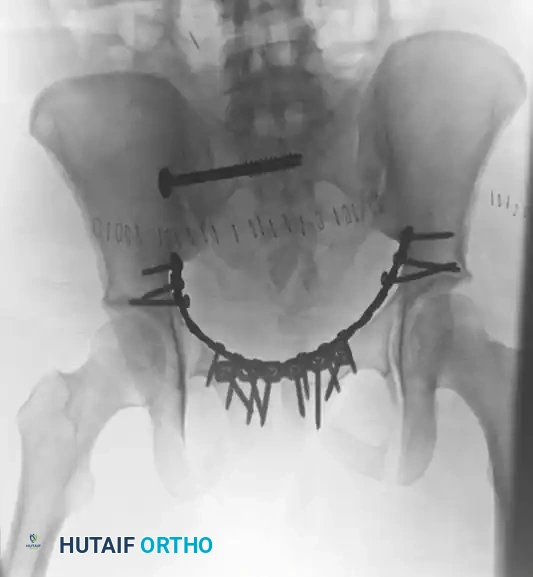

The following radiographic series demonstrates the successful transition to definitive internal fixation in a vertically unstable pelvic fracture, utilizing an anterior symphyseal plate and a posterior sacroiliac screw:

TREATMENT Surgical Diagram

Postoperative Outlet view. This projection assesses the superior-to-inferior (vertical) displacement of the hemipelvis and confirms the extra-foraminal trajectory of the sacroiliac screw, ensuring the S1 and S2 nerve roots are protected.